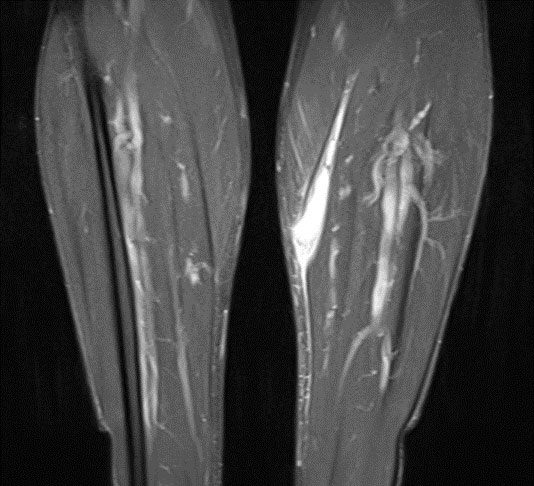

The MRI scans of the left lower leg obtained after the injury demonstrated a substantial, semi-circumferential medial fluid collection along the superficial soleus fascia. There was oedema within the medial head of the gastrocnemius which showed a circumscribed haematoma measuring 12 x 29 mm. In addition, there was an extensive lamella of fluid extending to the anterior margin of the tibia. The retracted tendon core of the medial head of the gastrocnemius was evident at the inferior margin of the haematoma, at the level of the middle third of the tibial shaft (Figs. 1 + 2).